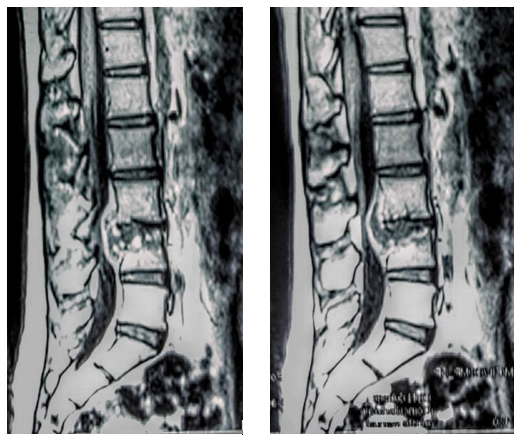

RNM columna lumbar: colección con señal de partes blandas heterogénea en T2, de localización epidural por detrás de L3-L4, sin compromiso aparente del disco intervertebral interpuesto, generando estrechamiento del canal raquídeo en contactocon las raíces de la cola de caballo. Se extiende por el neuroforamen derecho hacia el espacio paravertebral, contactando con el músculo psoas homolateral (Fig 1).

Figura 1: RNM columna vertebral